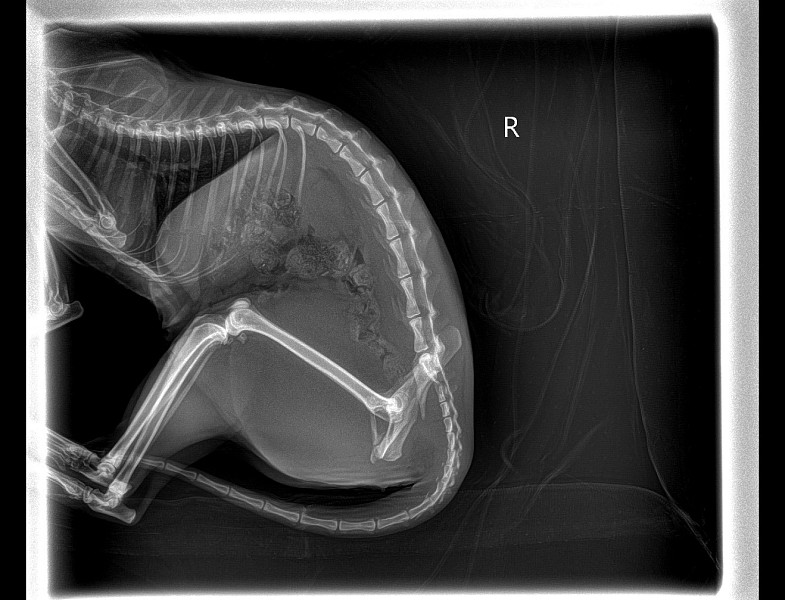

Перелом таза у собаки